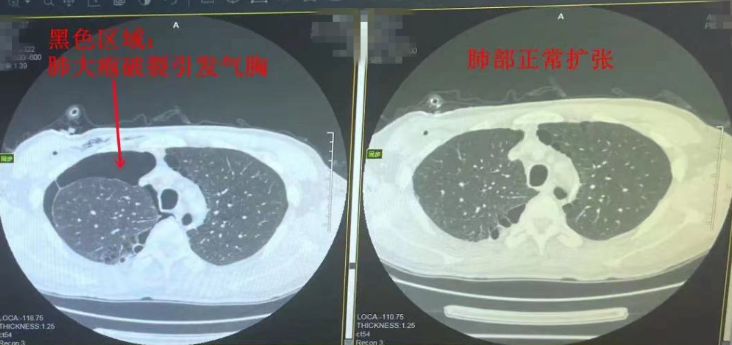

前不久,李先生因咳嗽后右侧胸闷不适来到南通六院就诊,接诊的胸外科张雪冬主任诊断其为肺大疱破裂导致气胸发作(右侧压缩40%)。 “他是做体力活儿的,这已经是他第4次气胸发作。之前最严重的一次,气胸发作压缩80%,气胸的反复发作严重影响了日常生活和工作。”李先生的爱人回忆,因不想动手术,一直以来他们都选择采取胸腔闭式引流治疗。为彻底解决气胸反复发作,这次李先生决定接受手术治疗。 胸外科张雪冬主任团队在胸腔镜下为其实施了“肺大疱切除术、肺减容+胸膜固定术”,术中楔形切除了肺大疱及部分发育不良、空泡样无功能的肺组织,使有功能的肺组织充分复张、发挥作用,从而有效改善了肺功能。同时在肺切缘处覆盖一层“牛心包”生物膜,减少术后发生肺泡漏,降低术后气胸复发风险。术后3个月复查,李先生恢复良好,胸闷得到明显改善,干活也有力气了。 “李先生有近30年的吸烟史,每天起码抽十几根。”张雪冬介绍,李先生肺上的空泡属于继发性肺大疱,它的形成与他长期吸烟密不可分。他表示,肺是由很多肺泡组成,长期吸烟会损伤气道粘膜细胞,引起气管和支气管狭窄,导致呼吸阻力变大,气体淤积在肺中不易排出,使得肺泡压力增大,再加上烟雾本身会使肺泡壁变得异常脆弱,长此以往肺泡壁破裂、相互融合,就会在肺组织内形成含气的囊腔,即肺大疱。 随着肺大疱逐渐增大,肺泡壁会变薄,在剧烈咳嗽、提重物或运动时,压力突然增加,肺大疱可能会破裂,引起自发性气胸,压迫到肺组织,进而出现胸闷、呼吸困难等症状。张雪冬表示,如果肺大疱不大,且没有症状,不影响正常生活,动态观察、定期随访即可。一旦出现胸闷、呼吸困难等症状,应及时就医。 张雪冬提醒,目前对于自发性气胸,虽然可以经胸腔闭式引流等非手术方法治疗,但如果气胸反复发作,还是应积极采取胸腔镜手术治疗,减少复发率,提高生活质量。此外,肺大疱属于不可逆的肺部病变,一旦形成,无法修复。如果肺大疱患者继续吸烟行为,肺大疱可能会进一步扩大,最终影响肺功能,进展成慢性阻塞性肺病,危害健康。